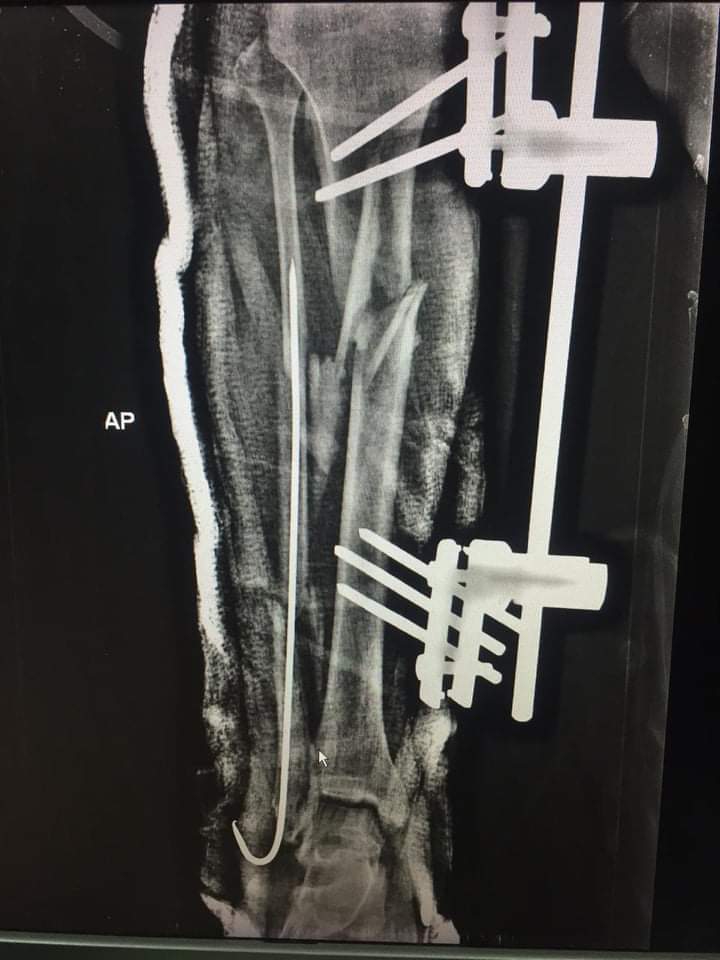

وأعلنت مديرية الصحة بجنوب سيناء أن المصاب حضر لقسم الاستقبال والطوارئ بالمستشفى بعد تعرضه لحادث طريق وبتوقيع الكشف والفحص الطبي عليه والإشاعات اللازمة تبين أنه يعاني من كسر مفتوح (مضاعف) من الدرجة الثالثة بالساق اليسرى مع تهتك شديد بعضلات مقدمة الساق مصحوب بضعف الدورة الدموية مع فقد جزء كبير من الجلد.

وتقرر تحضير المصاب للعمليات لإجراء جراحة عاجلة لإنقاذ ساق المصاب من البتر، حيث جرى تنظيف وتطهير الجرح المتهتك ووضع المضادات الحيوية الموضعية وإزالة الأنسجة التالفة وتثبيت الكسر المضاعف بواسطة المثبت الخارجي، وسلك معدني للشظية.